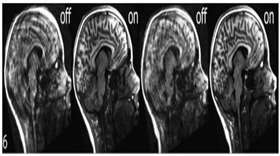

② 뇌영상 데이터 (.nii / .nii.gz / .csv)

뇌영상 데이터

구분 항목 대상자 비고

뇌구조 MRI 영상 TI 254명 1인당 362개 정보

뇌기능 MRI 영상 EPI 254명 1인당 7000장 이상

c Rest 뇌 휴지기 영상

d T1 뇌 구조 영상